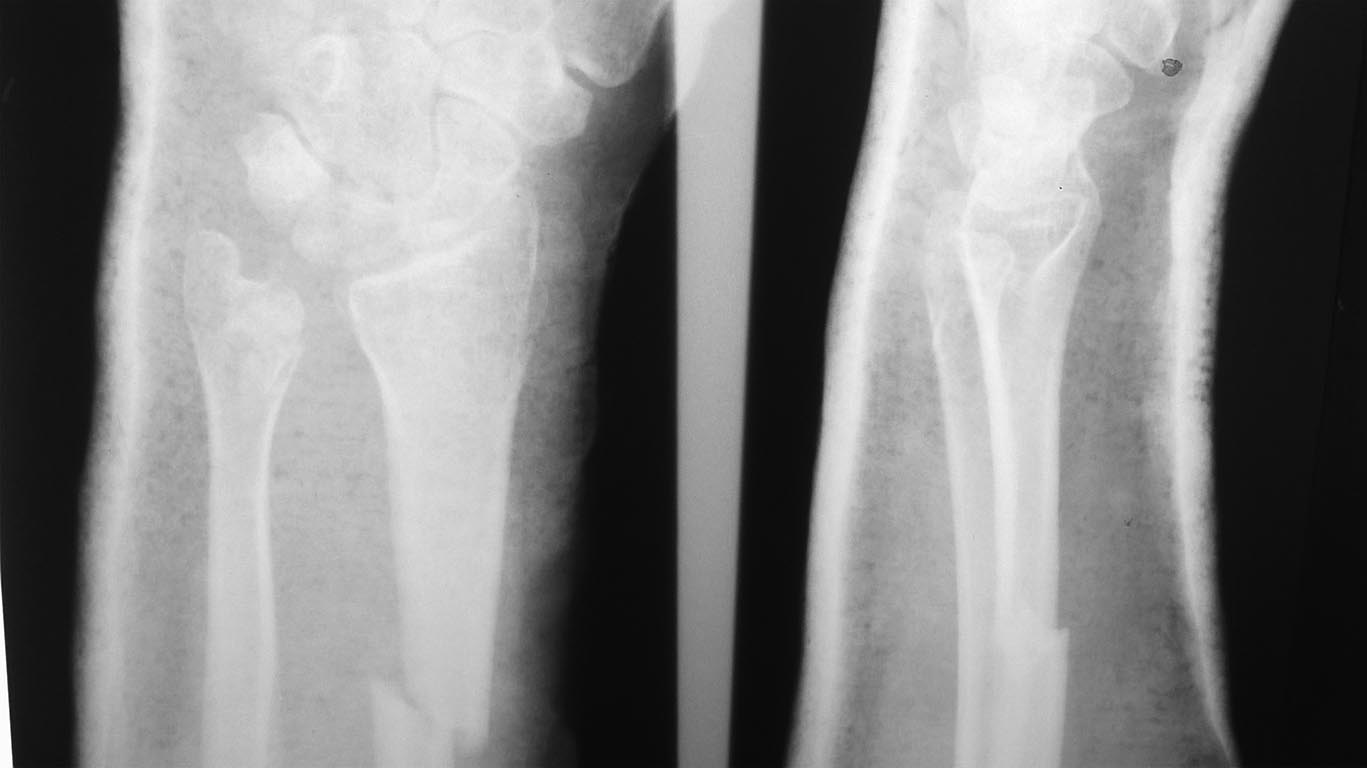

К нам поступила женщина с закрытым переломом диафиза лучевой кости и

переломом головки локтевой кости с повреждением дистального

радиоульнарного сочленения.

В плане открытый накостный остеосинтез лучевой кости. Нужен совет по

поводу вмешательства на локтевой кости,если на интраоперационных снимках

подвывиха головки локтевой кости не будет